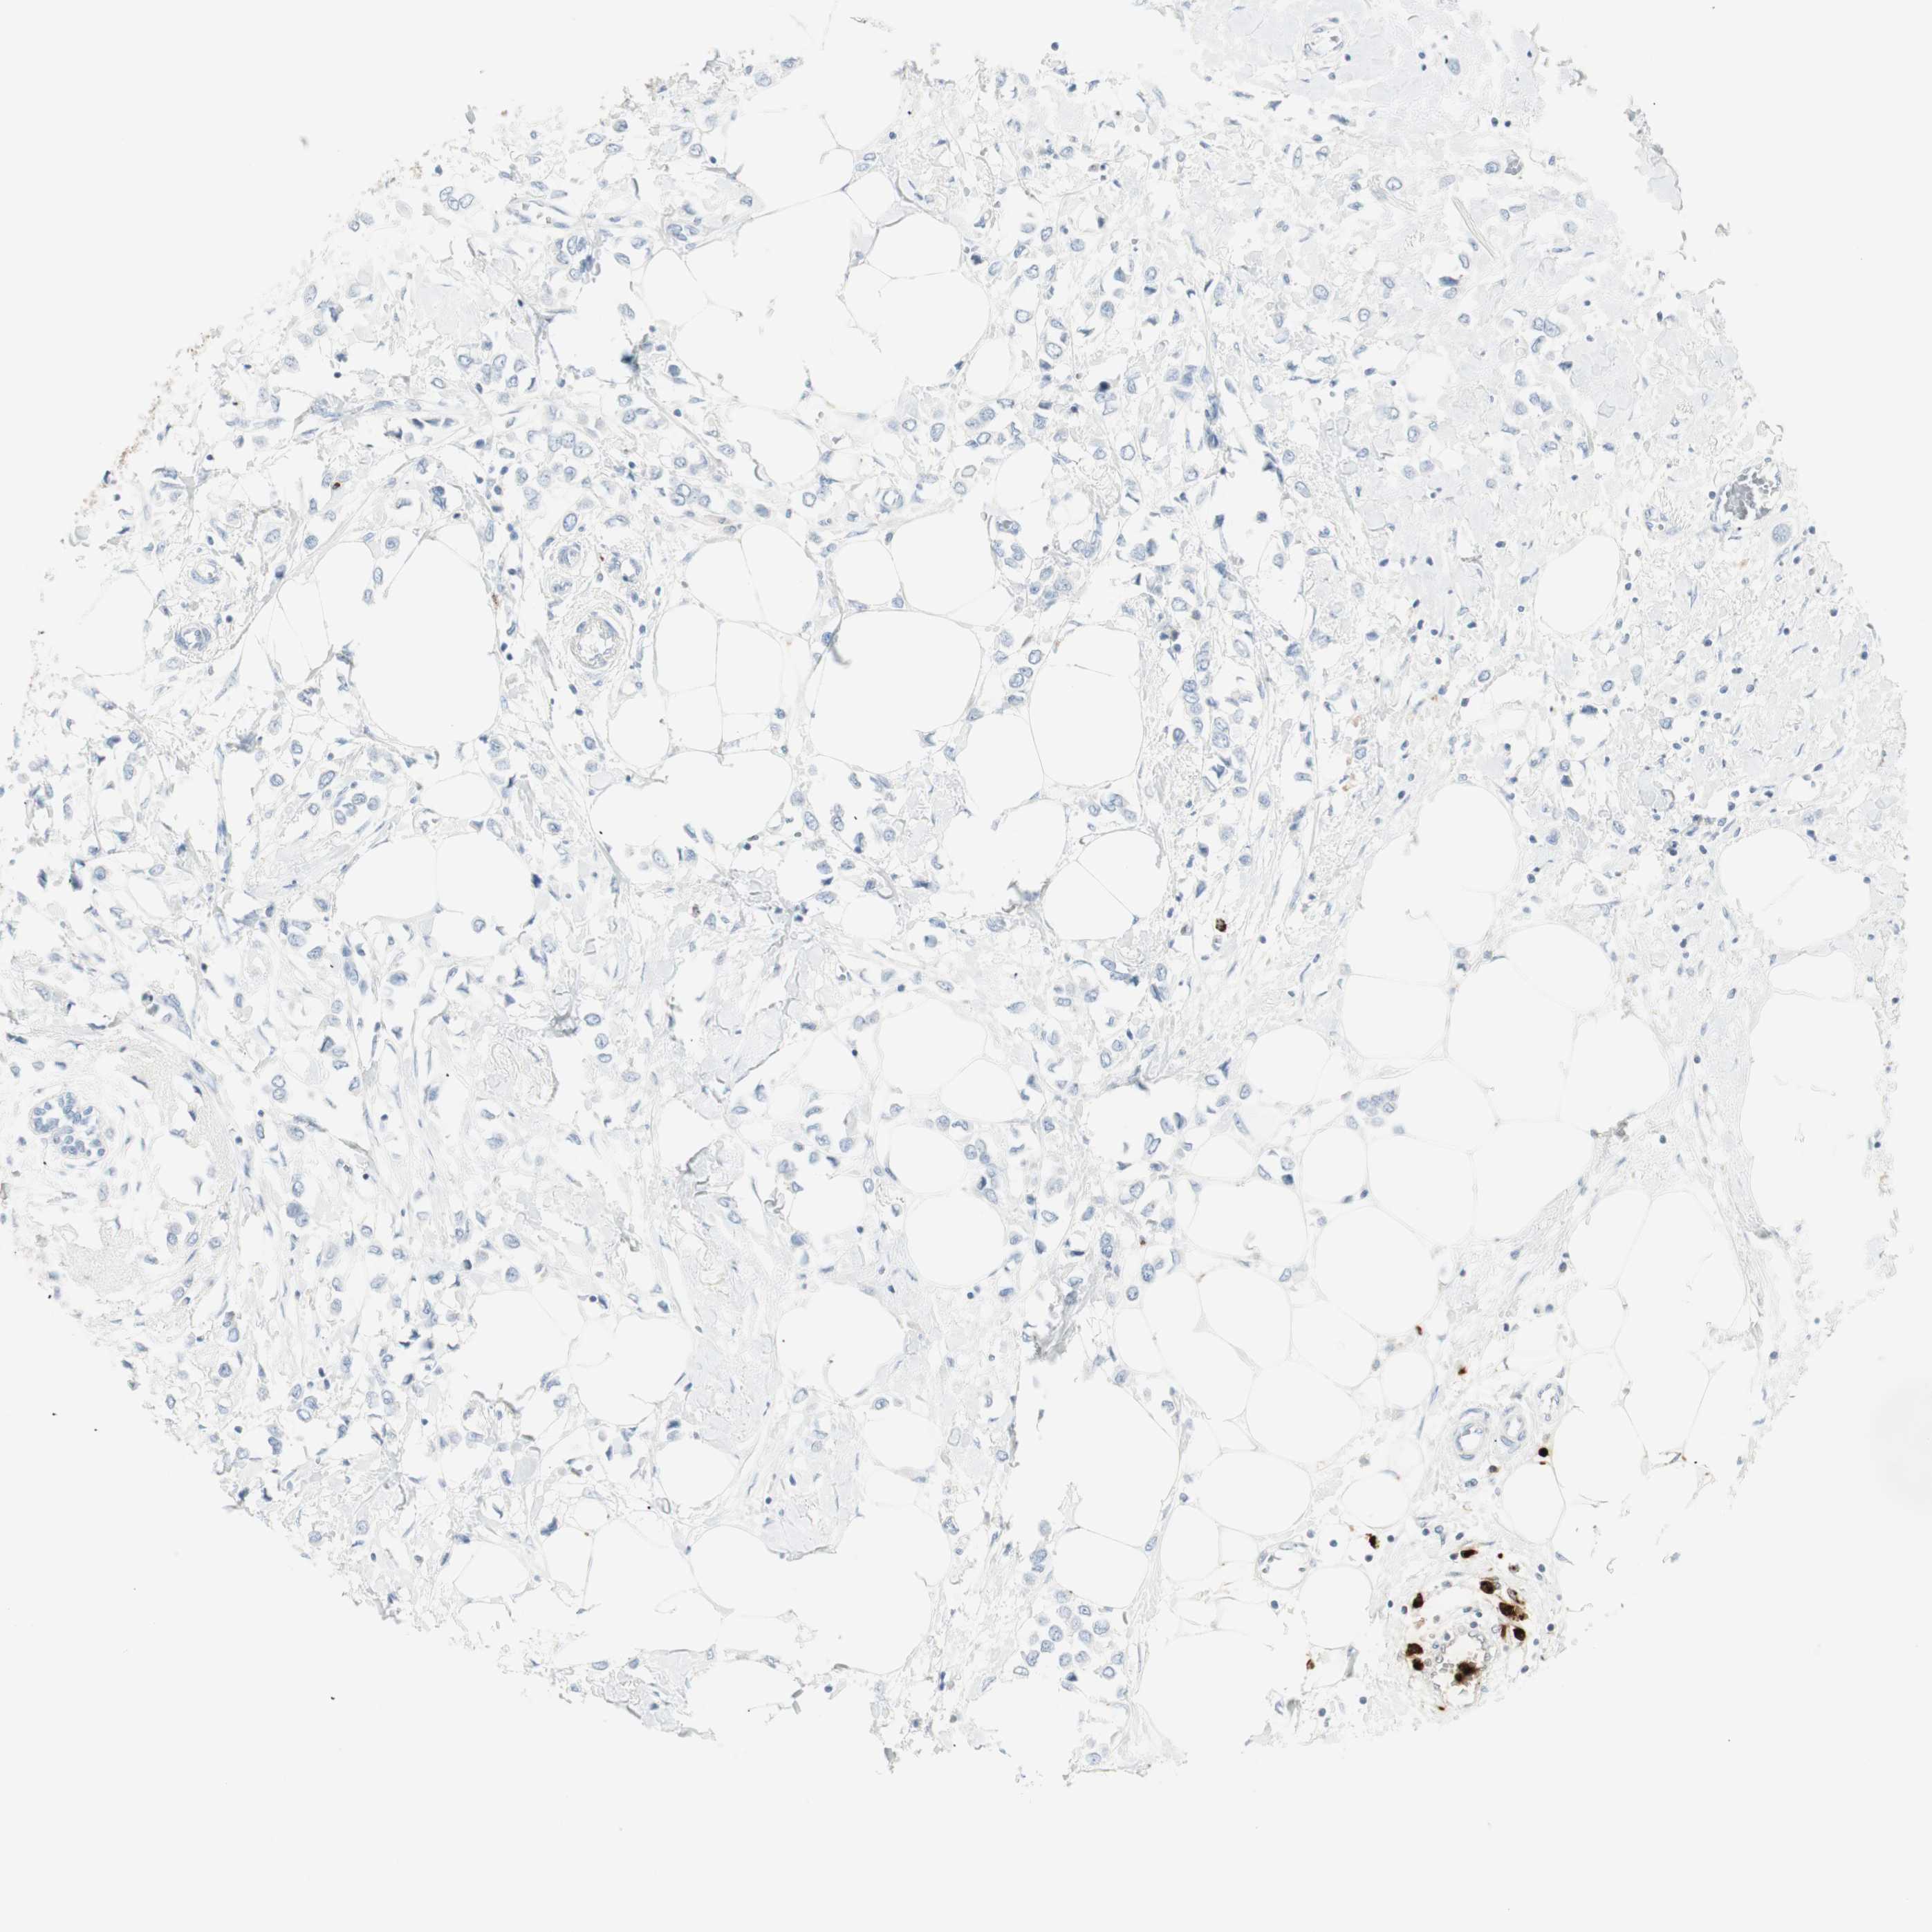

BRCA TCGA BRCA VALIDATION PROTEIN EXPRESSION

ANTIBODIES

AND

VALIDATION